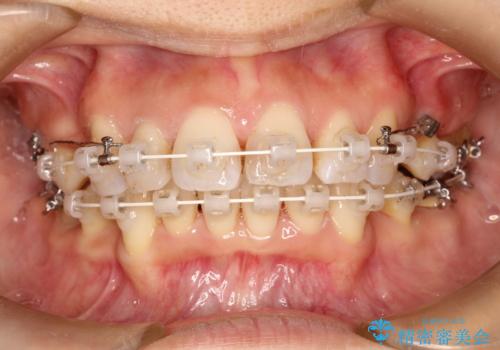

ワイヤーによる抜歯矯正でガタガタと深いかみ合わせの改善

- 上下の歯のがたつきを主訴に来院されました。

上下の前歯の叢生とかみ合わせが深い過蓋咬合という状態でした。

上下左右の歯を1本ずつ抜歯して、ワイヤーにて矯正を行いました。